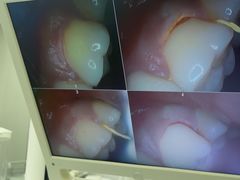

• 牙博士口腔品牌连锁(杨浦店)

• -牙博士口腔品牌连锁(杨浦店)